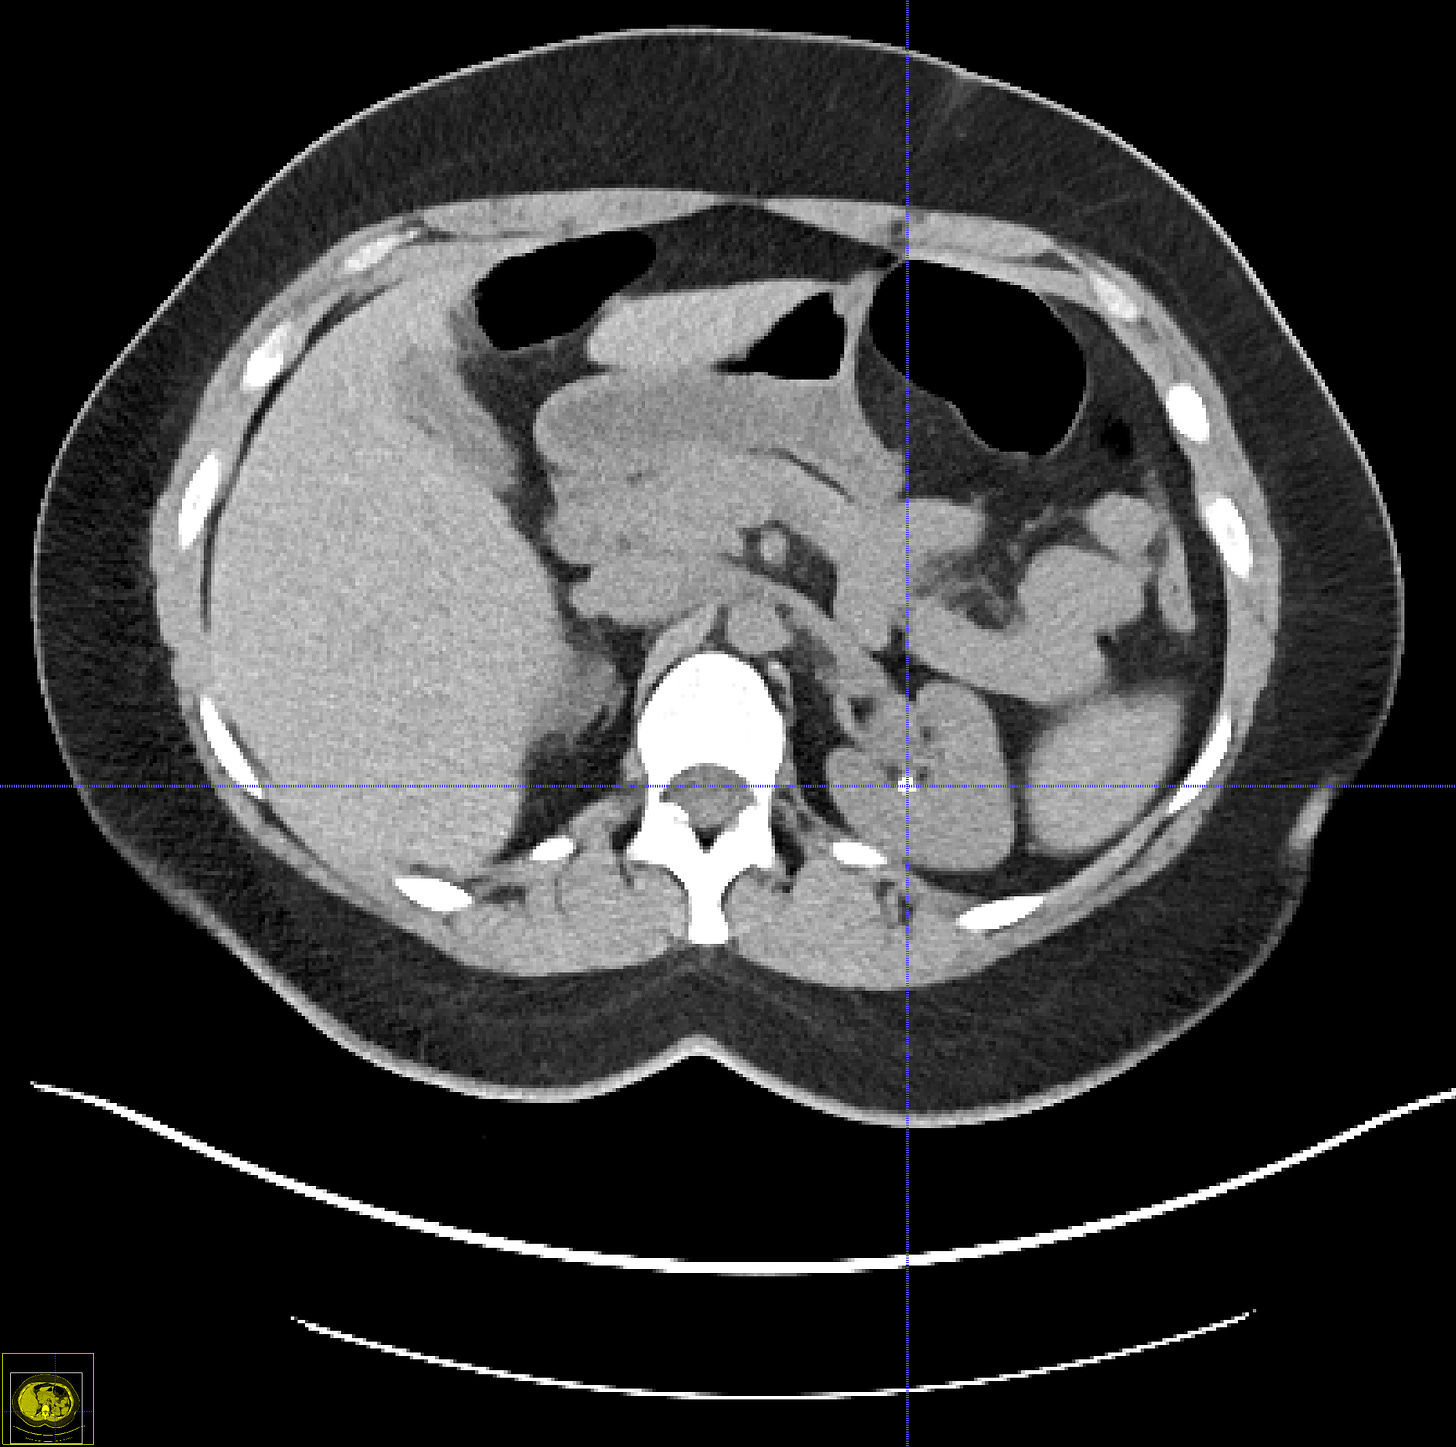

In the first part of this post I’ll go over the evidence for extreme pain events. Then, I’ll focus on kidney stones. The main reason for focusing on kidney stone pain is that over the past two years I’ve worked off-an-on on automated deep learning based software for detecting and measuring kidney stones in CT scans (see my paper in Medical Physics). So I have some expertise on the subject. Currently I am working with a radiologist at Massachusetts General Hopsital who is an expert on stone disease, Prof. Avinash Kambadakone.[1]

Several imaging techniques exist to screen for kidney stones—kidney-ureter-bladder (“KUB”) X-ray radiographs, ultrasound, MRI, and CT (colloquially called “CAT scanning”). A nice summary of the pros and cons of these different techniques is shown in this table:

The technique with the highest sensitivity is CT followed by MRI, which doesn’t involve any radiation dose but is roughly three times as expensive. Only CT is useful for detecting small stones (< 4 mm) and uric acid stones (which comprise about 15% of stones and are transparent on radiographs).[5]

For screening purposes, CT and ultrasound are only two viable options. The main issue with CT is radiation doses, which increases cancer risk to a non-trivial degree. However, low dose screening protocols have been developed and validated (I won’t bother my readers with technical details here, although I personally find them fascinating). The bottom line is that screening protocols now exist where the radiation exposure is on par with a KUB radiograph (about 1.5 mSv).[6] Adoption of these protocols has been slow, however. The effect of low dose radiation on cancer risk is somewhat controversial but 1.5 mSv given to people with an age around 50 would increase their lifetime cancer risk by about 1 in 10,000. In other words, you would get one new cancer for about every 10,000 scans performed. This is pretty non-trivial and further Fermi estimates are needed here to understand benefits vs risks.

How many kidney stones might we detect early via CT scanning? Potential kidney donors typically undergo a CT scan to screen for potential counter-indications. Studies show that about 7.5% of potential donors have previously undiscovered kidney stones.[7] Some transplant centers allow donors with kidney stones to donate, others do not. Many people get CT colonographies around age 60. When a CT colonography is performed, the radiologist is responsible not just for analyzing the colon but also for doing due diligence on the rest of the scan. In my work at NIH, I looked at 5,381 CT colonography scans that had reports available. Among those, 755 had keywords suggesting the that a kidney stone was found (15 %). [8]These scans were all from ~10 years ago, so current numbers might be a bit higher.